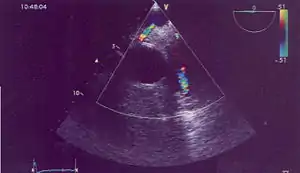

| Possible communication between left coronary artery and pulmonary artery in a 45-year-old woman with Bland-White-Garland syndrome. | |

Historically ALCAPA was diagnosed with conventional angiography. Today echocardiography is easily used. It can provide direct visualisation of the anomalous coronary artery and other associated structural abnormalities, and it can also assess myocardial function. The use of pulse and color-flow doppler can sometimes visualise reversal flow in the pulmonic artery. Other non-invasive methods used are computed tomography (CT) as well as magnetic resonance imaging (MRI) which enable a direct visualisation of the arteries as well as the myocardial viability.[3]